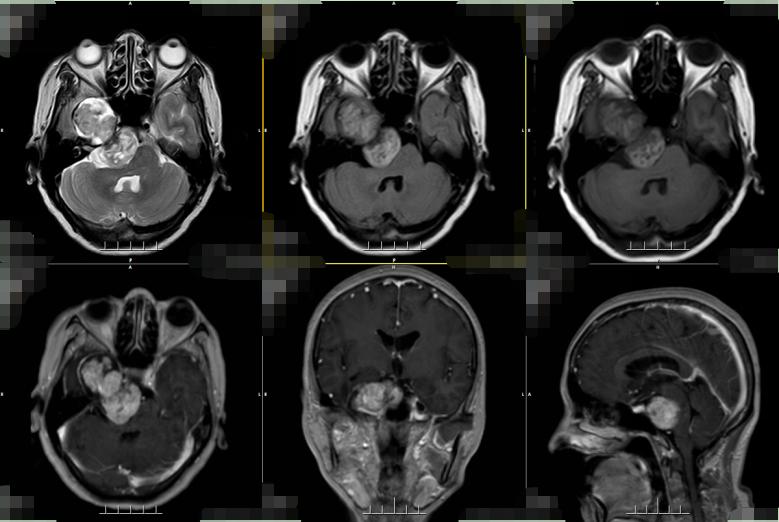

根据患者的症状描述与影像资料,与脑膜瘤、听神经瘤等鉴别诊断后,我院神经外六科主任吴杰考虑患者是右侧跨颅中窝、颅后窝肿瘤(三叉神经鞘瘤)。

▲术前检查

虽然基本确诊为三叉神经鞘瘤,但治疗却不易。患者的肿瘤较大,周围血供丰富,已经侵犯三叉神经,同时压迫邻近颈内动脉、右侧大脑中后动脉主干。吴杰介绍,“患者的肿瘤骑跨颅中、颅后窝,手术切除难度高。”颅后窝空间狭小,分布各种颅神经,稍有不慎将伤及周围神经或脑干,一次性全切手术难度系数和面临的风险巨大。